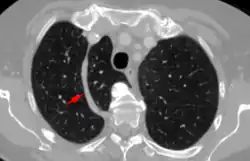

Azygos lobe

In human anatomy, an azygos lobe is a normal anatomical variation of the upper lobe of the right lung.[1] It is seen in 0.3% of the population.[2] Embryologically, it arises from an anomalous lateral course of the azygos vein,[3] in a pleural septum within the apical segment of the right upper lobe or in other words an azygos lobe is formed when the right posterior cardinal vein, one of the precursors of the azygos vein, fails to migrate over the apex of the lung and penetrates it instead, carrying along two pleural layers as the azygous fissure, that invaginates into the upper portion of the right upper lobe.[1]

An azygos lobe is usually an incidental finding on chest x-ray or CT scan. It is asymptomatic and not associated with any morbidity.[4][5] However, it can cause technical problems in thoracoscopic procedures.[6] The presence of the azygos lobe could alter the normal location of the superior vena cava or may be associated with other anomalies, including esophageal atresia or intrapulmonary right brachiocephalic veins.[7]